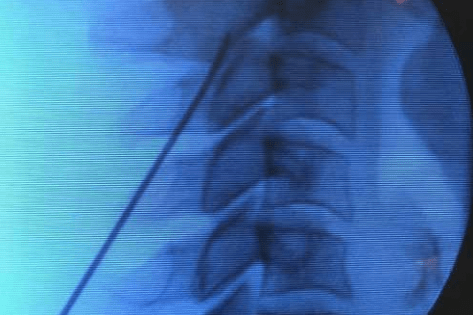

O que é a neuroestimulação? A neuroestimulação é uma técnica médica que utiliza impulsos elétricos de baixa intensidade para modular a atividade do sistema nervoso central e periférico. Ao interferir com os sinais de dor que vão da periferia do nosso corpo para o cérebro, este tratamento oferece um alívio significativo e duradouro para muitas […]